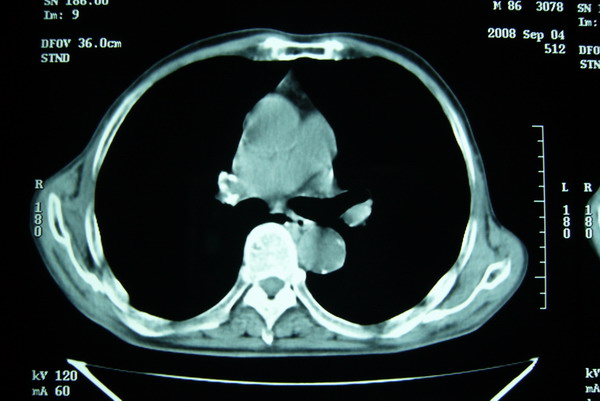

标题: CT15579:男 86岁 咳嗽 咳少量白痰 发热2天 吸烟史60年 [打印本页]

标题: CT15579:男 86岁 咳嗽 咳少量白痰 发热2天 吸烟史60年

右上周围型肺癌,慢支,肺气肿。

分叶及少量边缘性钙化,老年人,周围性肺癌首先考虑。

右肺上叶巨大软组织肿块,轮廓不规则,纵隔内有肿大淋巴结,首先考虑肺癌。

右上肺一不规则团块,边缘有分叶和毛刺,纵隔有淋巴结肿大。右肺周围性肺癌首先考虑。